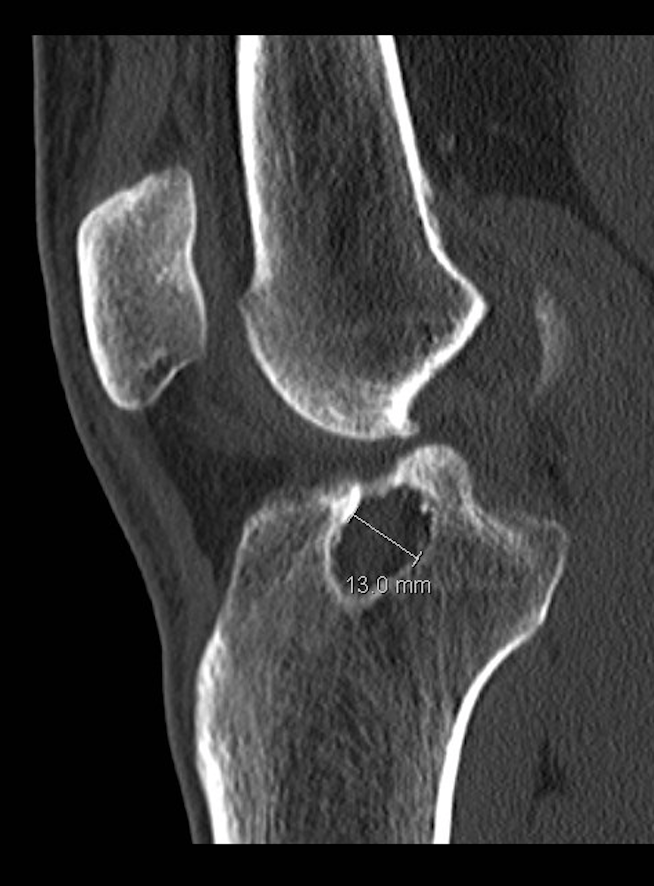

- Αξονική τομογραφία:

- Συχνά απαιτείται αξονική τομογραφία, ανάλογα με το μέγεθος και τη θέση των σηράγγων στις ακτινογραφίες

- Αυτό θα βοηθήσει στην παροχή πιο λεπτομερών πληροφοριών σχετικά με το μέγεθος και τη θέση των σηράγγων που είναι ο βασικός καθοριστικός παράγοντας για το αν η αναθεώρηση της ανακατασκευής του πρόσθιου χιαστού μπορεί να πραγματοποιηθεί σε ένα ή δύο στάδια

- Διεύρυνση σήραγγας (βλέπε παρακάτω)

- Διεύρυνσης σήραγγας:

- Οι σήραγγες όταν κατασκευάζονται είναι κυλινδρικές

- Με την πάροδο του χρόνου οι σήραγγες μπορεί να διευρύνονται και να αυξάνουν τη διάμετρο τους, ιδίως μεταξύ των ανοιγμάτων, δηλαδή μεταξύ της εισόδου και της εξόδου της οστικής σήραγγας στο μηρό και την κνήμη

- Επιθετική αποκατάσταση

- Εάν αυτή η διεύρυνση είναι >10-12 mm σε διάμετρο, τότε η εκτέλεση της αναθεώρησης σε ένα στάδιο είναι πιο προβληματική καθώς η σήραγγα θα είναι μεγαλύτερη από το μόσχευμα προκαλώντας προβλήματα στην τοποθέτηση, τη στερέωση και τη χαλάρωση: